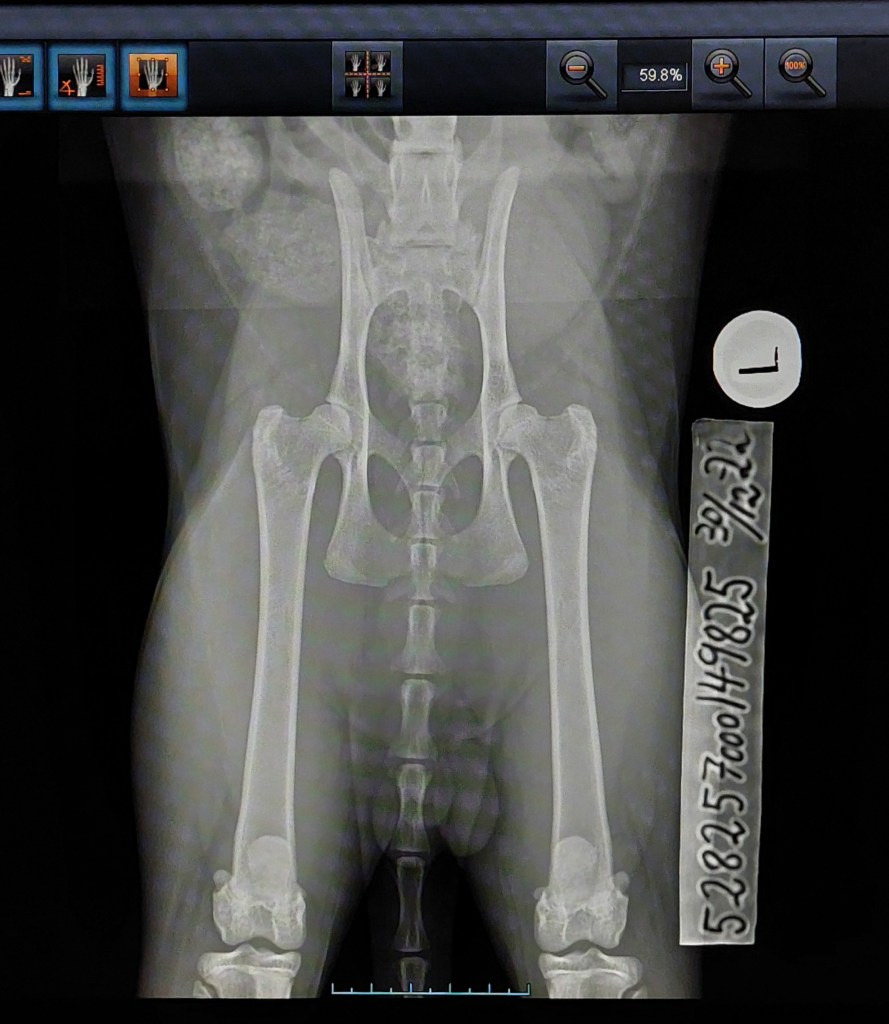

Along with Nylah I brought Rigo to his hip x-ray. I think his hips looks rather promising, so I dare to hope for normal hips – fingers and toes crossed ❤ His pictures has also been sent to PawPeds. – Rigo had to retake his pictures due to wrong ID-tape.

Results below.

The results weren’t what I hoped for, but still something I can work with. His results from PawPeds were mild dysplasia grade 1-1. I still want to compare results with OFA, so the pictures will be sent there for a second evaluation.